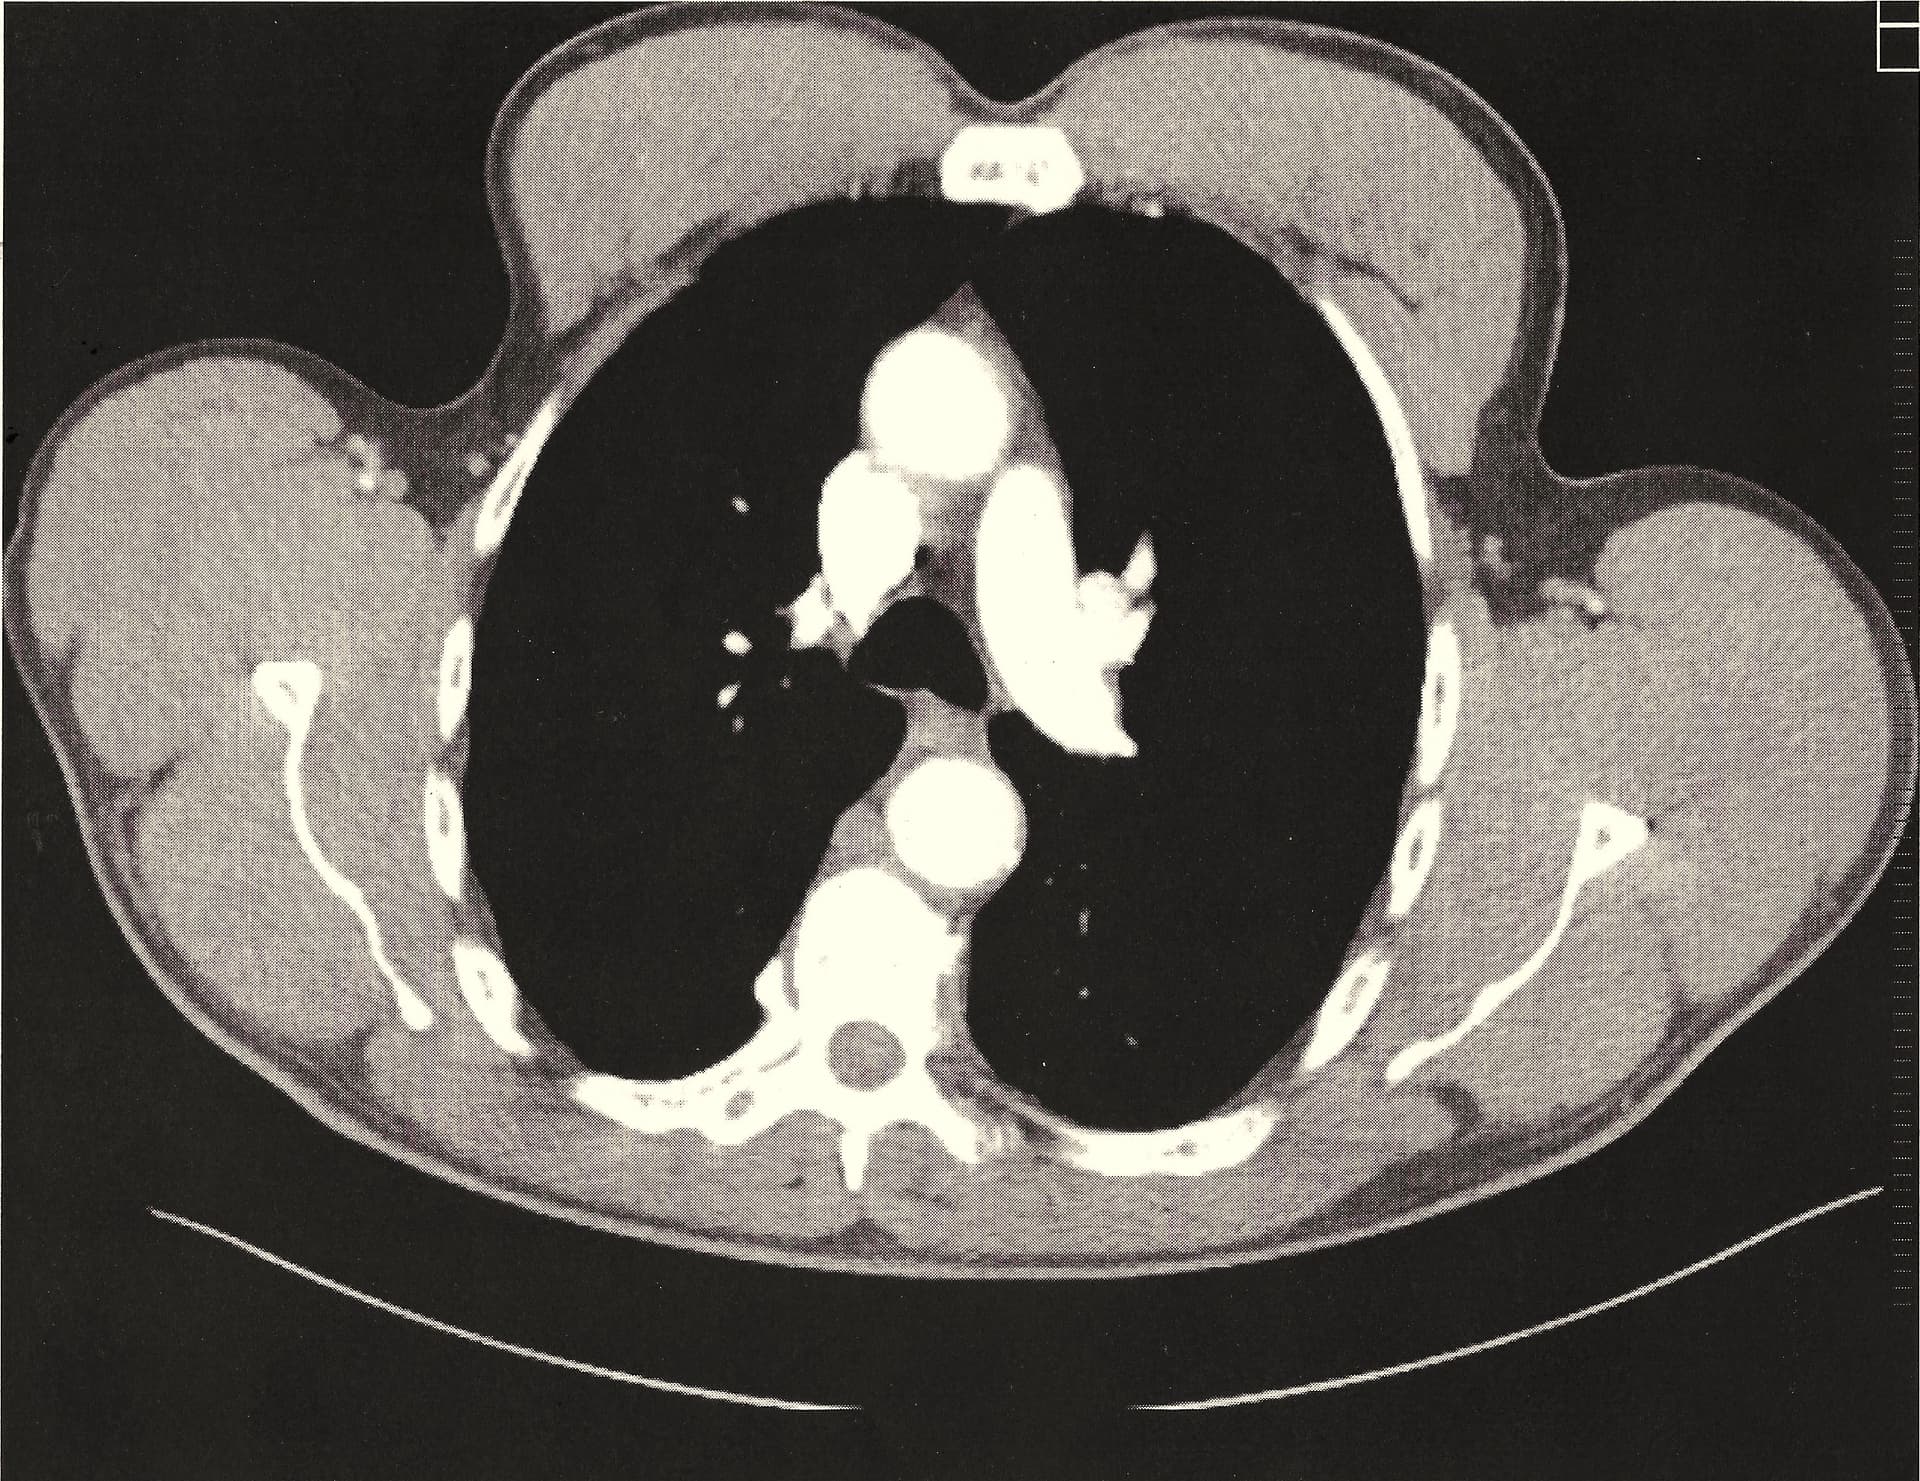

Let’s compare a healthy thymus on the left image in the article to a less healthy thymus on the right.

Use the above image as a reference – I did not outline my thymus - it shape is pretty obvious.Click to increase size and detals. Excellent scan.